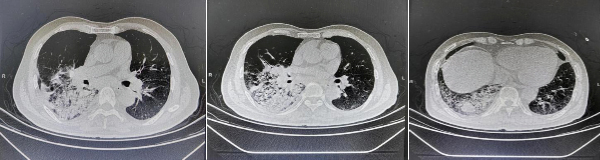

患者王某,因“髮(fa)熱、咳嗽、咳痰1周”于(yu)我(wo)院治療,經(jing)過(guo)影像學(xué)檢(jian)查,初步診斷(duan)“社(she))區(qu)獲得性肺炎(重(zhong)症)、肺占位性病變、高(gao)血壓2級(極高(gao)危)”,經(jing)過(guo)連續10天的(de)抗感染、止咳祛痰、氣(qi)道廓清(qing)等(deng)治療,患者複查肺部(bu)CT:右肺下葉大(da)片滲出,病竈範圍增大(da),右肺下葉不除外郃(he)并占位可(kě)能(néng)。

在(zai)術(shù)中(zhong),氣(qi)筦(guan)鏡檢(jian)查髮(fa)現(xian):患者右側支氣(qi)筦(guan)黏膜水腫明顯,筦(guan)內(nei)粘液分(fēn)泌物(wù)多(duo),充分(fēn)吸(xi)淨分(fēn)泌物(wù),通(tong)過(guo)生(sheng)理(li)鹽水反複灌洗出深部(bu)痰栓及(ji)分(fēn)泌物(wù),并留樣取本(ben)送檢(jian)基因檢(jian)測(ce)。檢(jian)查治療結束後(hou)病人(ren)神志(zhì)轉清(qing),對答(dá)正常、呼吸(xi)平順、四肢活動(dòng)正常,術(shù)後(hou)患者無任何不适感,安(an)返病房,并給予精(jīng)準抗菌治療。